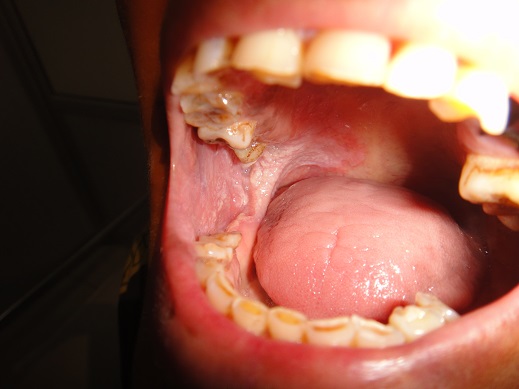

82 years old female suffering from soft palate carcinoma.CT scan shows the tumour arising from soft palate and involving the uvula.Pt has no significant lymph nodes.considering the age of the patient wide excision of the soft palate with primary closure of the soft palate done.patient has diabetes and hypertension.Her echo shows the LVEF 45%with sclerosis of the valves.